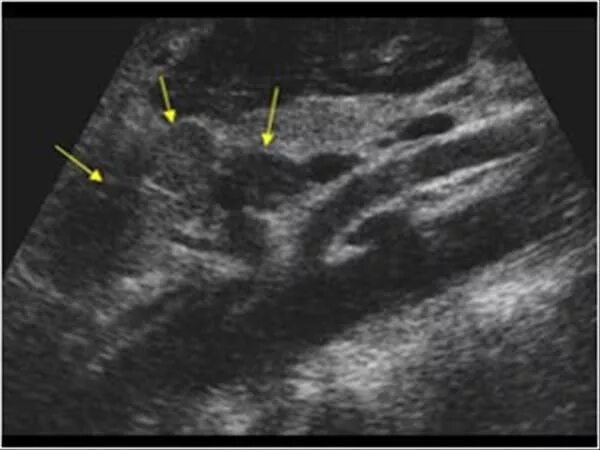

Метастазы в паховых лимфоузлах